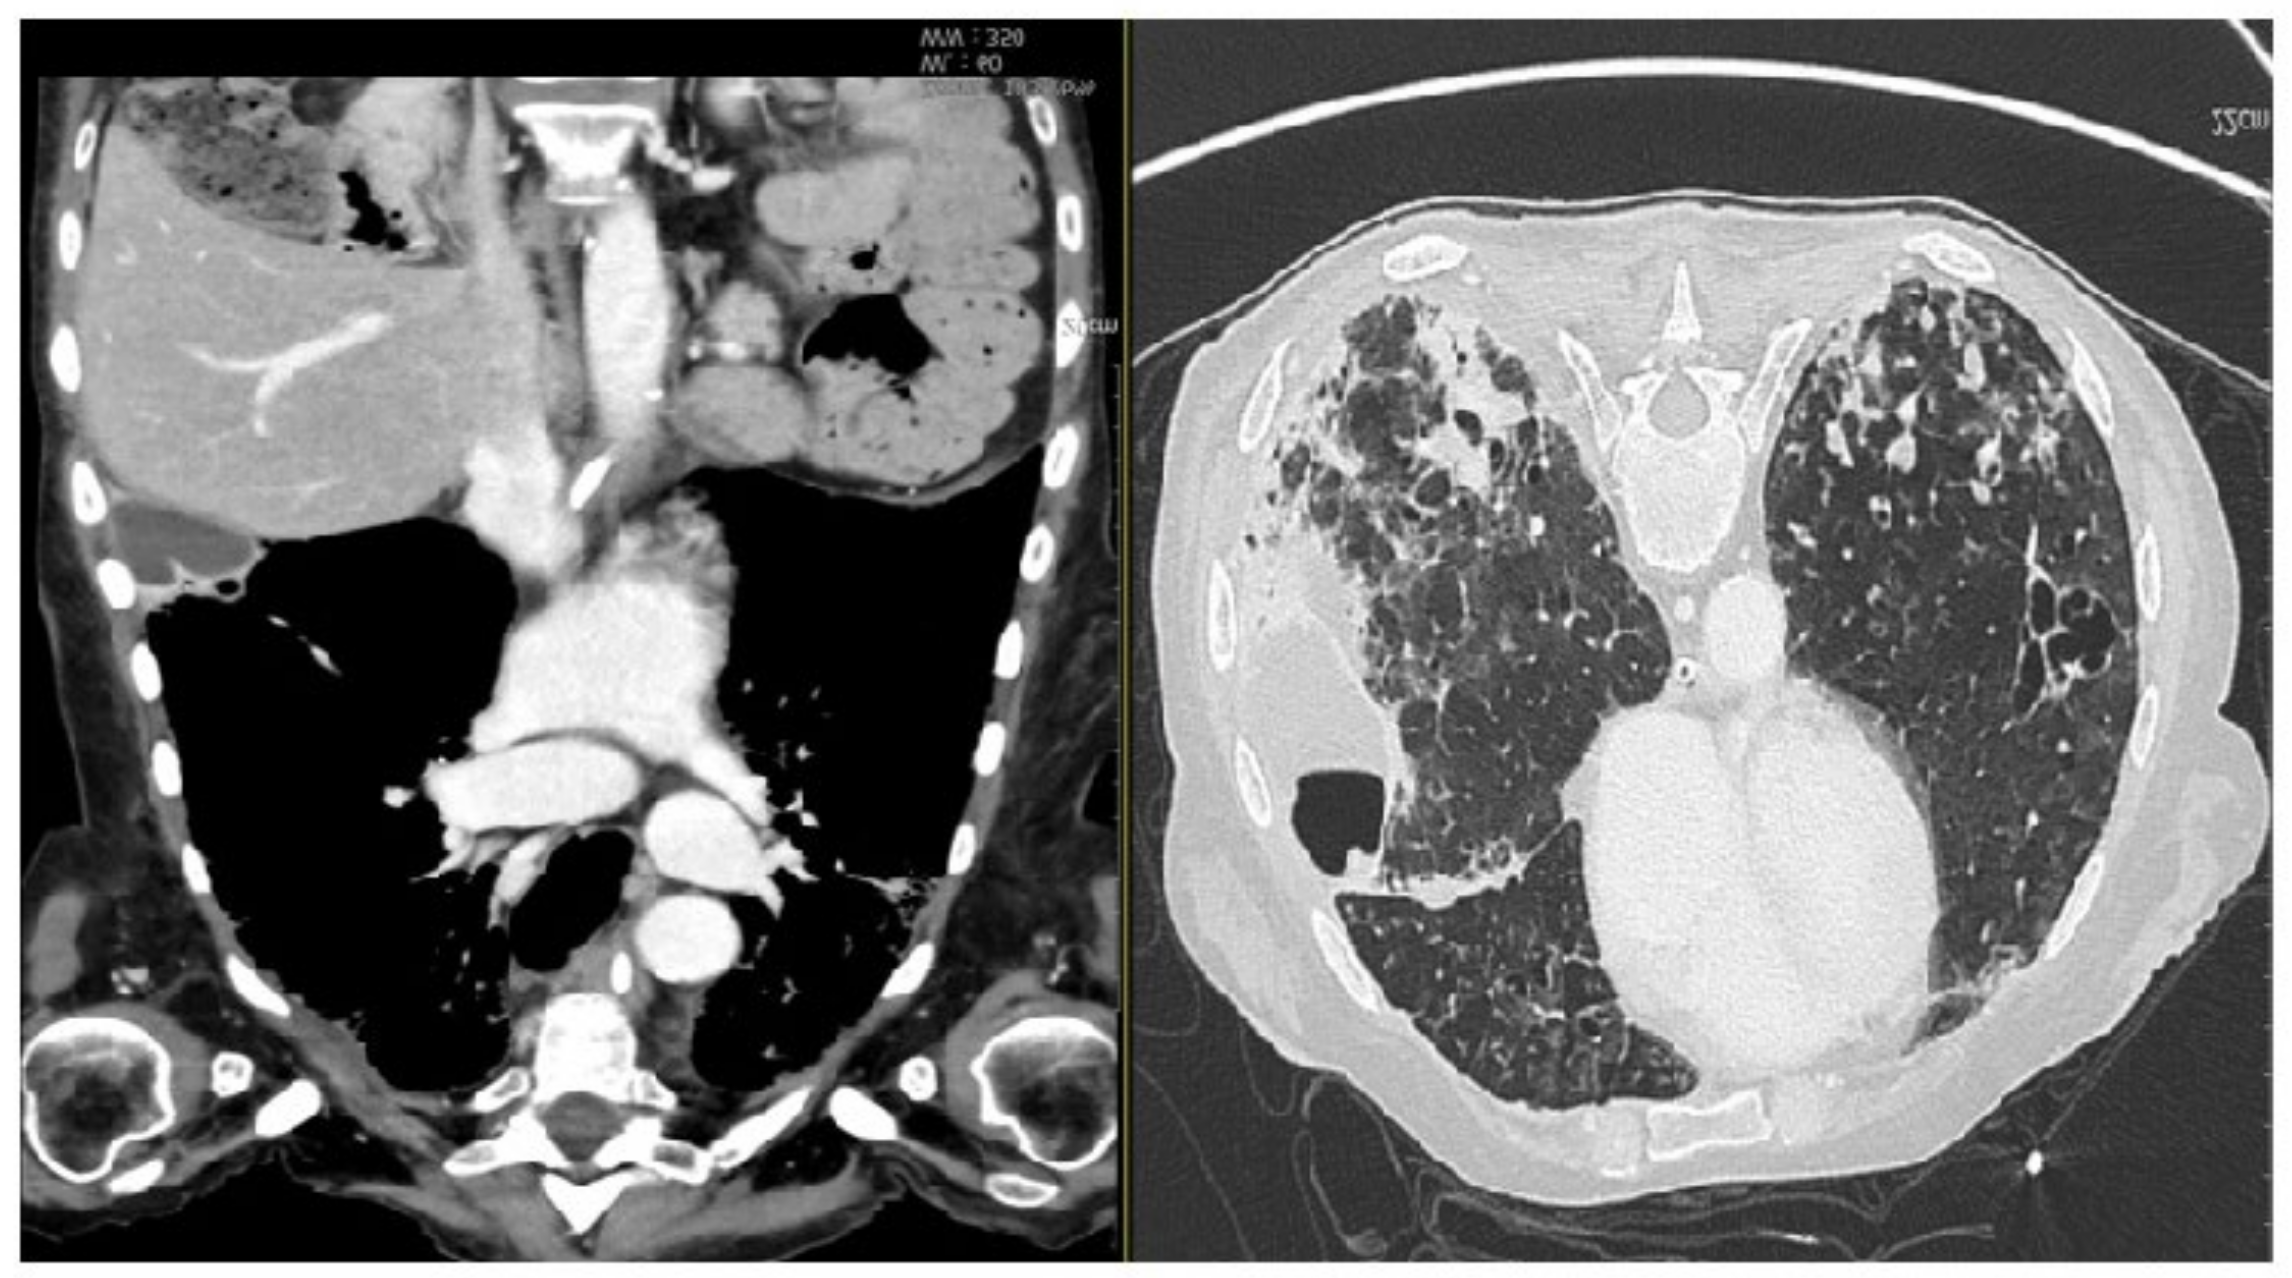

Figure 2.

CT scan showing (during hospitalization) pneumonia by Cytomegalovirus. At the lateral-basal segment of the right inferior lobe, in the subpleural level, the gross intraparenchymal collection with hydro-aerial content is compatible with the pneumatocele. In the lung window, multiple areas of parenchymal thickening are visible in the right basal location. (On the left, coronal section parenchymal window, on the right, axial section lung window). Partial laryngectomy (OPHL II B) with bilateral selective neck dissection (cervical nodal Robbins levels II–IV) and postoperative radiotherapy were planned to manage this case. Unfortunately, this planned surgical intervention was impossible because of the patient’s poor general conditions. Moreover, one of the follow-up CT scans of the chest (three months after the initial one) revealed the presence of bilateral diffuse multiple micronodules, which were considered early distant metastasis from the laryngeal adenoid cystic cancer (Figure 3).